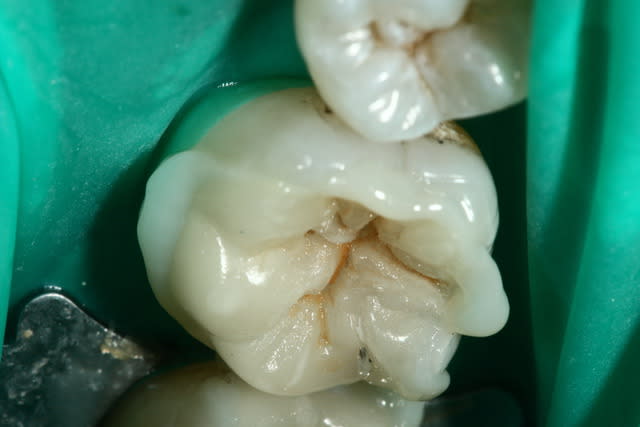

Puisque tout le monde montre des photos, à mon tour.

Il m'aura quand même fallu un petit moment avant de réussir à faire des onlay qui ressemble à quelque chose... Comme quoi, c'est pas que le prothésiste qui bosse!

Par contre me former ça commence à me coûter cher... Je ne fait presque plus de SPR50/SPR57...